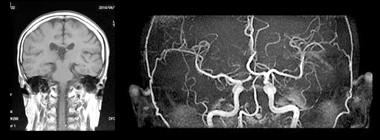

MRI検査

放射線を使わずに磁場と電波を使って体の中を見るため、被ばくが無く安全な画像診断装置です。主に脳卒中や認知症に関わりのある脳血管障害の早期発見などに有用です。